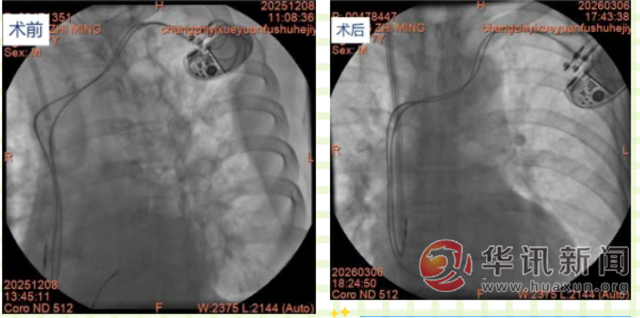

近日,肾病学科在心内科、介入科的紧密协作下,成功为一名77岁老年男性患者实施DSA下右颈内静脉半永久导管置入术。该患者因尿毒症维持血液透析治疗,需建立长期稳定的血管通路,既往有三度房室传导阻滞病史,并于3个月前置入永久心脏起搏器,此次需建立的半永久导管需精准避开起搏器导线区域,手术难度与风险极高,若操作不当,极易导致起搏器导线移位、脱落,引发严重心律失常。

手术当日,在DSA室精准影像引导下,肾内科手术团队凭借扎实的专业功底和丰富的复杂手术操作经验,术中全程实时监测起搏器工作状态,心内科王俊莉主任团队全程值守,密切关注各项生命体征变化。经过医护团队的紧密配合与精准操作,仅用1小时便顺利完成手术,导管位置精准达标,未对永久起搏器导线造成任何影响,患者术中无明显不适,生命体征全程平稳。